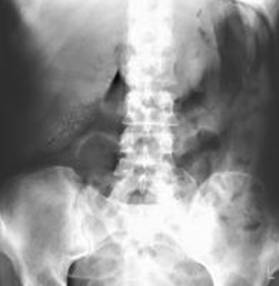

1.3.3-Radiogramma diretto dell'addome

L'esame radiografico dell'addome viene effettuato principalmente per escludere alcune diagnosi differenziali. Tuttavia vi sono alcuni segni radiografici indicativi di colecistite acuta:

Dilatazione di anse intestinali (segno di un possibile ileo paralitico);

Colecisti a porcellana (segno di una già pregressa colecistite cronica);

Possibile visualizzazione di un calcolo in sede colecistica (perché ciò avvenga il calcolo deve essere radiopaco e ciò avviene in circa il 15-20% dei pazienti)

Gas nella parete della colecisti (segno indicativo di colecistite enfisematosa). 9 ,10

Fig .1 Radiogramma diretto di paziente con colecistite enfisematosa

si noti la presenza di aria nella parete della colecisti

Fig 2 radiogramma diretto dell'addome. Numerose formazioni all'ipocondrio di destra